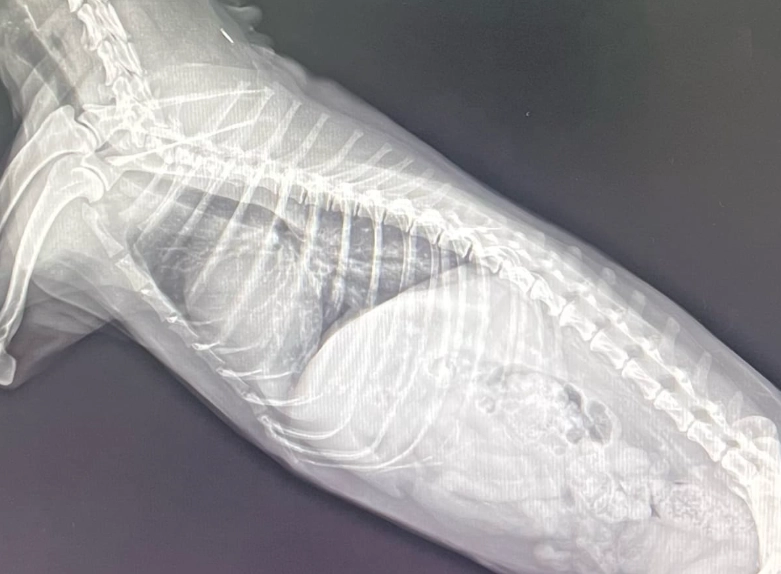

第二步:影像學檢查——胸腔X光。 這是診斷肺積水的黃金標準。在X光片上,正常的肺部是黑色的(充滿空氣),積水的肺部會出現白色、雲霧狀的區域。獸醫可以從分布位置(是瀰漫性還是局部?)初步判斷原因。